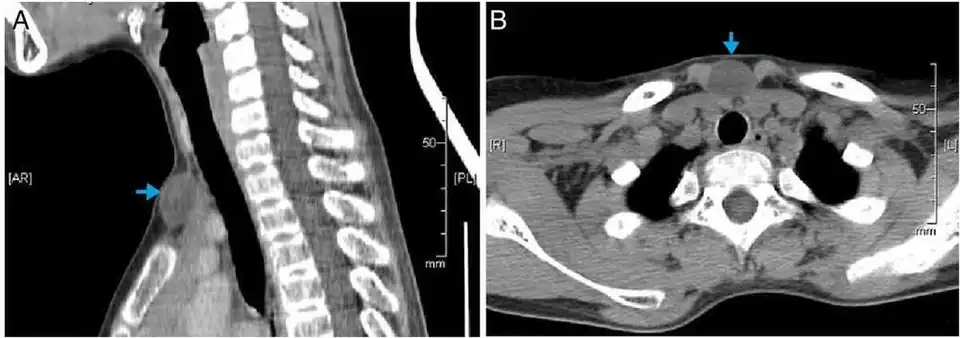

CT scan, showing a homogenous hypodense volume (unspecific cyst-like)

CT scan, showing a homogenous hypodense volume (unspecific cyst-like) -